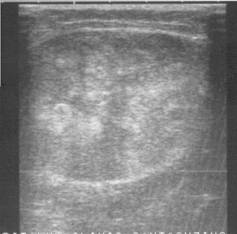

Fig. 19.6 Osteosarcom de coapsa.

Fig. 19.7 Metastaze hepatice de la osteosarcom de coapsa.